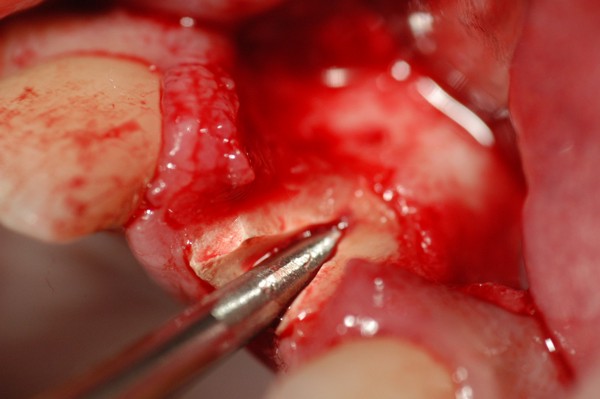

Abstract: Las fuerzas anterógradas traumáticas son en general las causantes de fracturas radiculares en el sector anterior de la boca. Desarrollo: El paciente se presenta a la consulta , con la fractura de una funda de porcelana inyectada en la zona cérvico palatina, solicitando simplemente la reparación en boca para evitar rozamientos linguales. Dicha funda con un perno colado en oro y su correspondiente endodoncia, habían sido realizadas en mi clínica varios años atrás, con un «aparente éxito total». Radiograficamente, se encuentra una fractura radicular cercana al tercio gingival Observada la oclusión de las piezas anteriores, podemos ver que el vínculo ideal de Acoplamiento, no se cumple, habiendo una relación de franco contacto la que ha provocado la fractura. Llevando al paciente a Oclusión en Relación Céntrica, podemos ver el espacio a nivel anterior, correspondiente a la centricidad mandibular. En esa misma posición , es dable percibir una faceta parafuncional mesial del primer premolar superior… …que antagoniza con una faceta parafuncional distal del canino inferior… ..constituyendo un plano inclinado que provoca la antelación mandibular o Discrepancia Horizontal, fracturando la raiz del incisivo central. Extraida la porción coronal de la raiz, pensamos en la realización de un Implante Inmediato, a pesar de la presencia de una fístula dado que se trataba de un central, decisión que obtuvo éxito implantario mas no estético, según veremos luego. Era fundamental conservar lo mas posible las tablas óseas, que de hecho había perdido la porción cervical Realizamos una incisión que conservara las papilas de las piezas adyacentes. Realizamos la exodoncia mediante un instrumento construido «ad hoc» que denomino: Con lo que obtenemos la preservación «ad integrum» de las corticales peridentarias remanentes. Instalamos entonces un implante T.B.R. de 15 mm de largo por 4 mm de diam. con cuello de zirconio de 3,5 mm …quedando tres espiras sin hueso por vestibular, producto de la tabla perdida, Incidimos el periostio a nivel apical del colgajo para obtener mayor paño quirúrgico, y legramos un bolsillo palatino sin incisiones de descarga, para la inserción de la membrana. Suplementamos la carencia ósea vestibular con «BIOSS» …e instalamos una membrana reabsorbible «BIOGUIDE» , que fijamos con el mismo implante, y calzamos por palatino. Suturamos Instalamos nuestra provisional previamente confeccionada, sobre un abuttment de titanio. Y controlamos radiograficamente Pasadas tres semanas del retiro de los puntos, observamos una cicatrización alta que nos muestra el anillo de zirconio del implante. ……………………………………………….. Transcurridos tres meses preparamos una nueva cirugía, dirigida a instalar un injerto autólogo de conectivo en el área del anillo, con un nuevo desplazamiento del colgajo vestibular. Tomamos tejido conectivo del paladar a nivel de los premolares, mediante una incisión mucosa «en libro», y disección del conectivo subyacente. Lo posicionamos en vestibular del anillo de zirconio y lo fijamos mediante sutura Y semanas después nos encontramos con un nuevo fracaso de orden estético. ……………………………………………….. En la actualidad, el caso esta estable , aún con su funda provisional, a la espera de un nuevo intento plástico, mediante Injerto Libre de Encia. ………………………………………………….. ESQUEMA MECÁNICO DEL FENÓMENO …que además de los hechos mostrados en el caso presentado, frecuentemente provocan en el sentido antero posterior los fenómenos de DISPERSIÓN ,en el maxilar superior…y de APIÑAMIENTO en el maxilar inferior. CONCLUSIONES: Además del rigor académico que nos convoca… esta; nuestra casa…nos otorga la confianza que solo da el saber que estamos siempre entre amigos, que cada vez son más. Por tanto es que debo decir: YO fui el responsable de dicha fractura… …porque… …..que hubiera sucedido si hubiera hecho todo el trabajo implantario sin ajustar previamente su oclusión? Seguramente a esta altura del caso…también hubiera fracasado el implante. Siempre decimos que se aprende de los errores más que de los aciertos, y Dr. Carlos A. Acuña Priano

Fig.11 Fig.12(Pie de foto: Incisión)

A.I.D.A.(Avulsionador Intradentario Atraumático.)

Fig.15 Fig.16(Pie de foto: A.I.D.A.)

Fig.17(Pie de foto: Preservación de la cresta remanente)